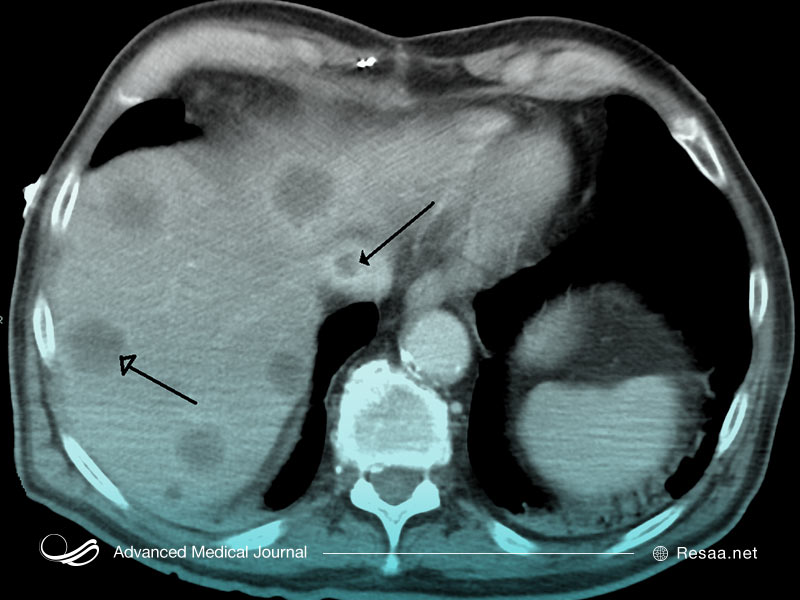

همچنین این امکان وجود دارد که پزشک به منظور کمک به تشخیص بیماری، اسکن تصویربرداری را تجویز کند. این موارد میتواند شامل اشعه ایکس “X-rays”، اسکن MRI و سی تی اسکن “CT scan” باشد. این تصاویر به پزشک شما کمک میکند تا به دنبال ناهنجاری در ساختار استخوان، بافتهای مغز، اندامها و اعصاب باشد.